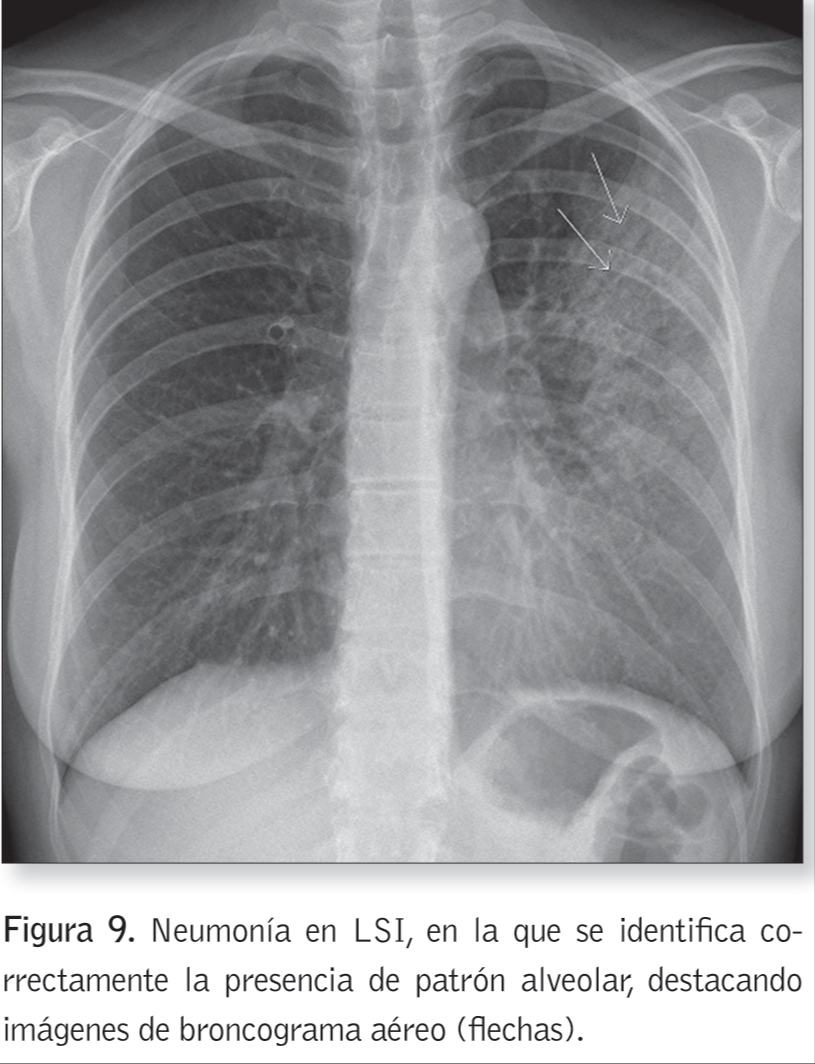

Patrón alveolar

¿En qué patologías podemos encontrar el patrón alveolar?

Edema pulmonar

Neunmonía organizada

Eosinofilia pulmonar

Sangrado pulmonar

Signo del broncograma aéreo